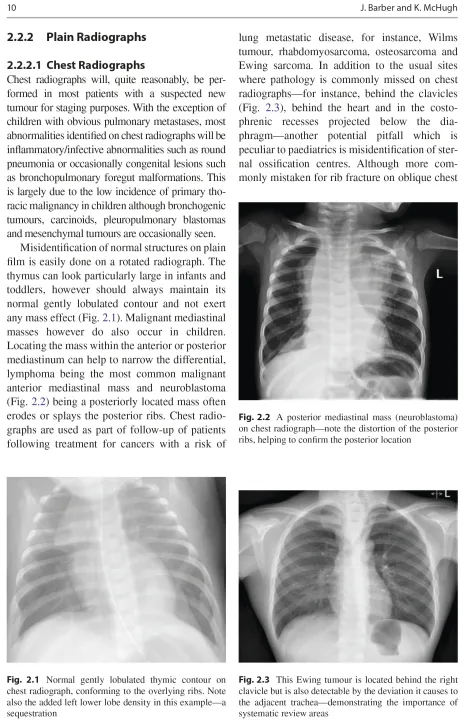

Sách Imaging in Pediatric Oncology (sách keo gáy, bìa mềm)

Year:2019

Edition:1st ed.

Language:english

Pages:402

This book, co-authored by an internationally acclaimed team of experts

in the field of pediatric oncologic imaging, provides a comprehensive

update on new advances in diagnostic imaging as they relate to pediatric

oncology. In contrast to other oncologic imaging texts focusing on the

radiology of specific tumors, this book emphasizes the important

fundamentals of imaging that every child with a new or treated

malignancy receives. Guidance is provided on the selection and use of

appropriate imaging techniques, with individual chapters devoted to each

of the major cross-sectional imaging modalities used in the detection

and follow-up of pediatric cancers, including PET-CT, PET-MRI,

whole-body MRI, and diffusion-weighted MRI. Additional nuclear medicine

techniques are addressed, and detailed attention is paid to more

advanced areas of practice such as contrast-enhanced ultrasound,

pediatric interventional radiology techniques, radiation treatment

planning, and radiation dose considerations (ALARA). Other areas covered

include screening of children with cancer predisposition syndromes,

treatment related complications, potential pitfalls during

neuro-oncologic imaging, and the risks and benefits inherent in

post-therapy surveillance imaging.